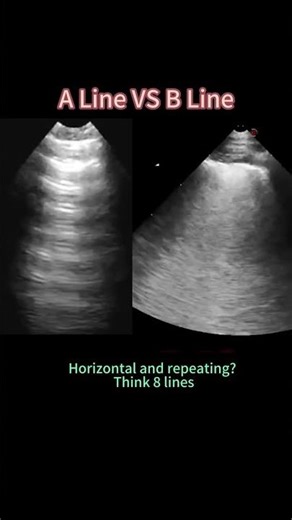

A-Lines vs B-Lines | How to Tell the Difference #ultrasound #sonograp